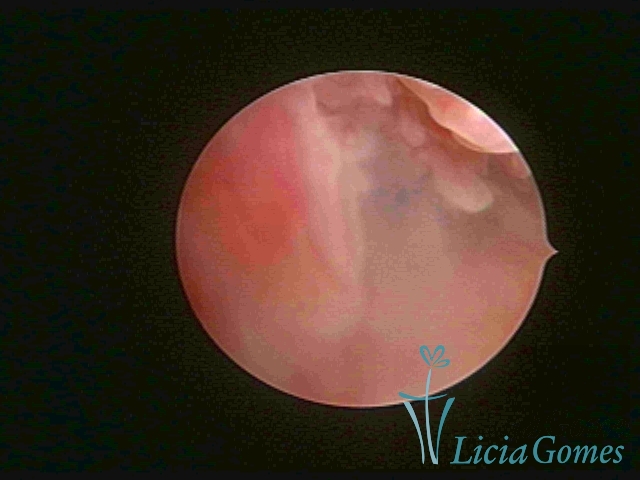

Third part or upper section

Presents the mucosa with a smooth, poorly vascularized surface, to the internal orifice